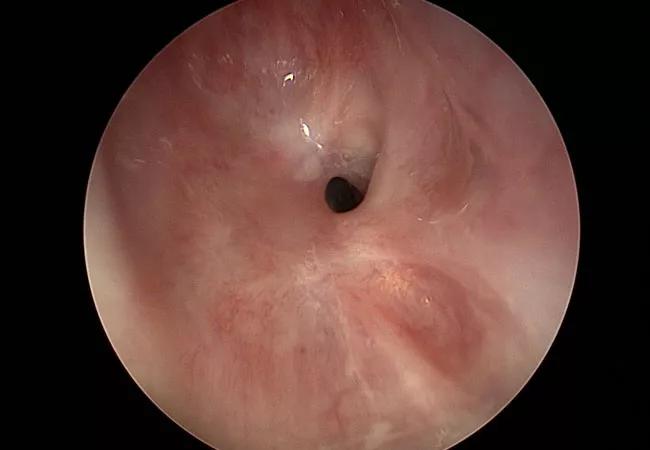

endoscopic Idiopathic Subglottic Stenosis

Subglottic stenosis is a narrowing of the larynx below the vocal cords, essentially blocking a patient’s airway. It can be caused by trauma (including from tracheotomy or intubation) or autoimmune disease (including granulomatosis with polyangiitis, sarcoidosis and systemic lupus erythematosus). However, in some cases, the condition is idiopathic.

For idiopathic (and some traumatic) subglottic stenosis, treatment often begins conservatively, with an endoscopic procedure.